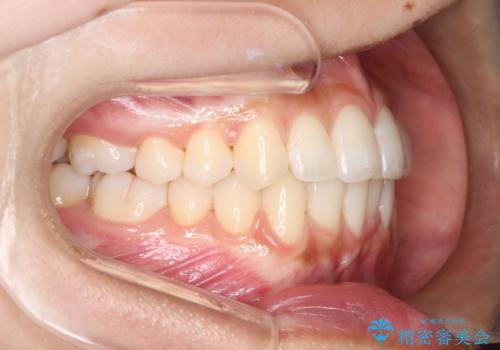

1年でここまで変わる。デコボコ歯並びの非抜歯矯正!

治療計画をしっかり立て、歯の移動量や力のコントロールを最適化することで、約1年という短期間で矯正治療を終了することができました。

治療後は歯並び・かみ合わせともに大きく改善し、患者様にも大変ご満足いただけました。